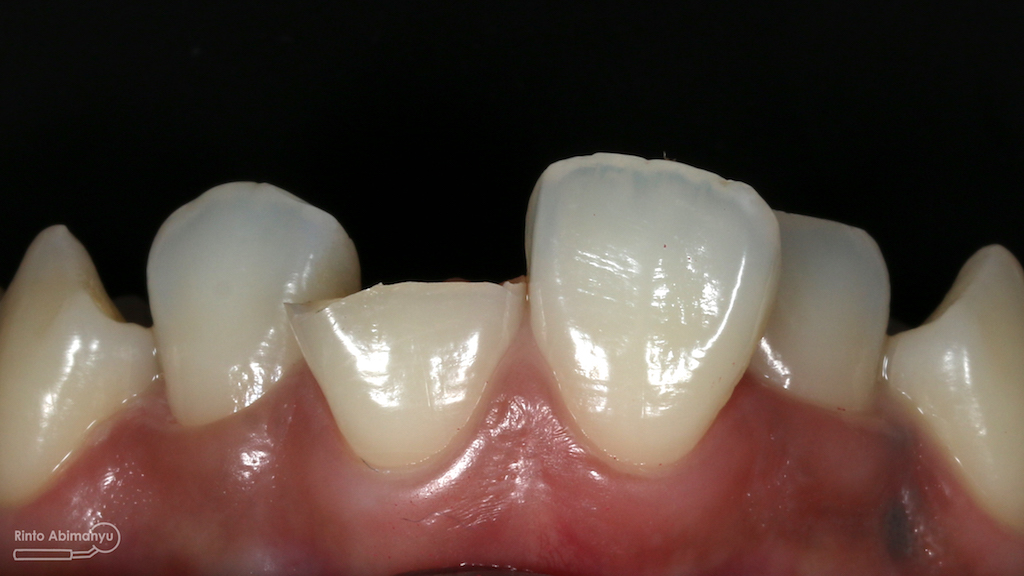

Begini kondisi klinis saat datang…

Foto klinis gigi-gigi anterior yang mengalami fraktur